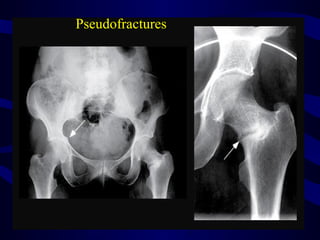

Pseudofractures

X - rays Osteomalacia •Osteopenia • Looser zone , • biconcave vertebra , • Spontaneous fractures